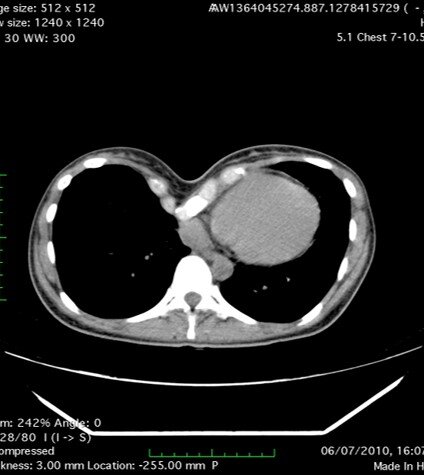

Для данной деформации характерно сочетание функциональных проблем (компрессия сердца, нарушение биомеханики дыхания) и психологических комплексов, обусловленных нарушенной эстетикой грудной клетки.

При беременности диафрагма поднимается, грудная клетка расширяется, что может стать причиной избыточного давления пластин в третьем триместре беременности.